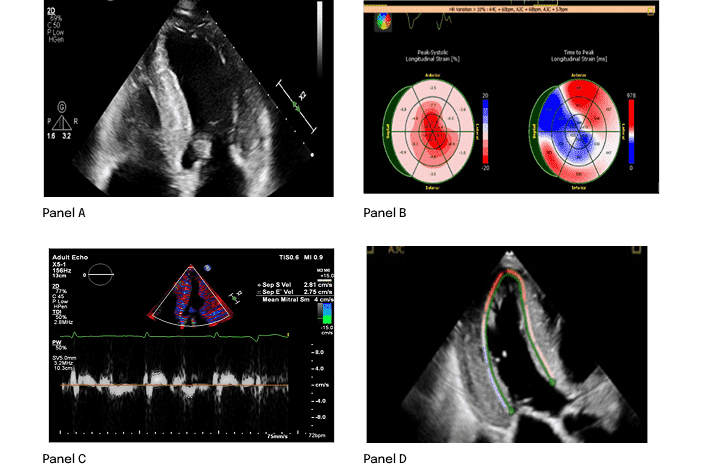

ÉCHOGRAPHIE4

- Phénotype hypertrophique avec manifestations infiltrantes

- Remplissage du VG restrictif et épaississement de la paroi du VD

- Faible vélocité de l’onde e' à l’anneau mitral septal ou latéral

- Réduction de la déformation longitudinale globale